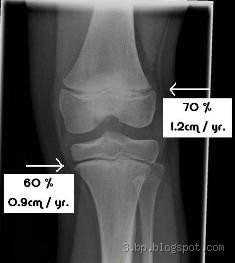

How Do Open Growth Plates Appear on X-rays?

I remember the first time I saw an X-ray of a friend’s growth plates – it was actually a little shocking. Open growth plates show up as gaps or lines between the bone’s shaft and its end (epiphysis). In contrast to closed growth plates, which look like solid bone, these open plates are more like a space filled with cartilage. On an X-ray, it might seem like a black line or a space between two bones. It’s like a little doorway for bone growth.